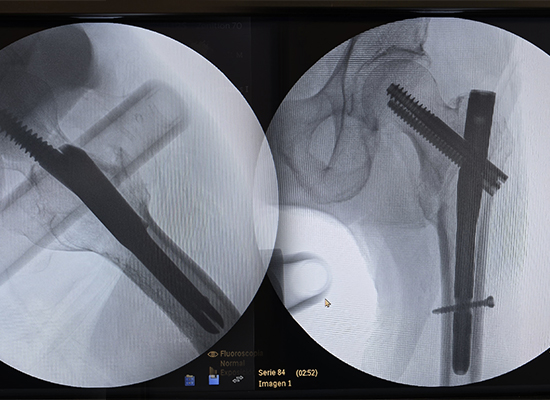

Radiografía posoperatoria que muestra la fijación con clavo intramedular Intertan de una fractura intertrocantérea izquierda, Perú

Durante la cirugía, el Dr. Rivera observó que el clavo intramedular CZMEDITECH Intertan proporcionó una estabilidad biomecánica superior y una implantación suave.

Esto facilitó una reducción estable y una fijación confiable, cumpliendo con las demandas biomecánicas del patrón de fractura.

La cirugía utilizó un sistema de clavo intramedular CZMEDITECH Intertan junto con su juego de instrumentos integrado.